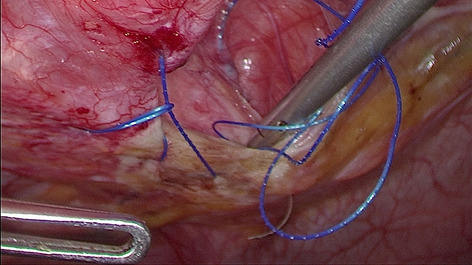

Until now there have been early attempts at producing advanced laparoscopic systems but these have been cumbersome and limited in their engineering. We present a revolutionary new advanced laparoscopic instrumentation system called ArtiSential. The ArtiSential instruments include bipolar forceps, Maryland dissector, monopolar spatula, monopolar hook, needle holder, with more on the way. They allow a wide range of articulating movement through 7 degrees of freedom that can mimic the dexterity of robotic platforms (Fig. 1). Traditional laparoscopic instruments have limited range of movements but these instruments allow for complex articulating movements in different planes which can be further exploited around the fulcrum of the port. This additional articulation means that there is better access to difficult part of anatomy. Furthermore, there is tactile feedback on the instrument handset which is lightweight and disposable.

Our initial series of cases include pelvic colorectal surgery and demonstrate the advantages of articulating instruments (Fig. 2). Further, we demonstrate that there is a learning curve to these instruments to maximise their benefit during complex procedures. We suggest adopting the formal training programme which includes a period of dry lab training before embarking on clinical cases so that surgeons may truly benefit from these advanced instruments. This also allows for safer introduction of new technology.

Advanced laparoscopic instruments such as ArtiSential should be used to make challenging aspects of laparoscopic surgery more accessible. These are not substitute for all straight instruments but best used to maintain precision during difficult manoeuvres in combination with traditional instruments.